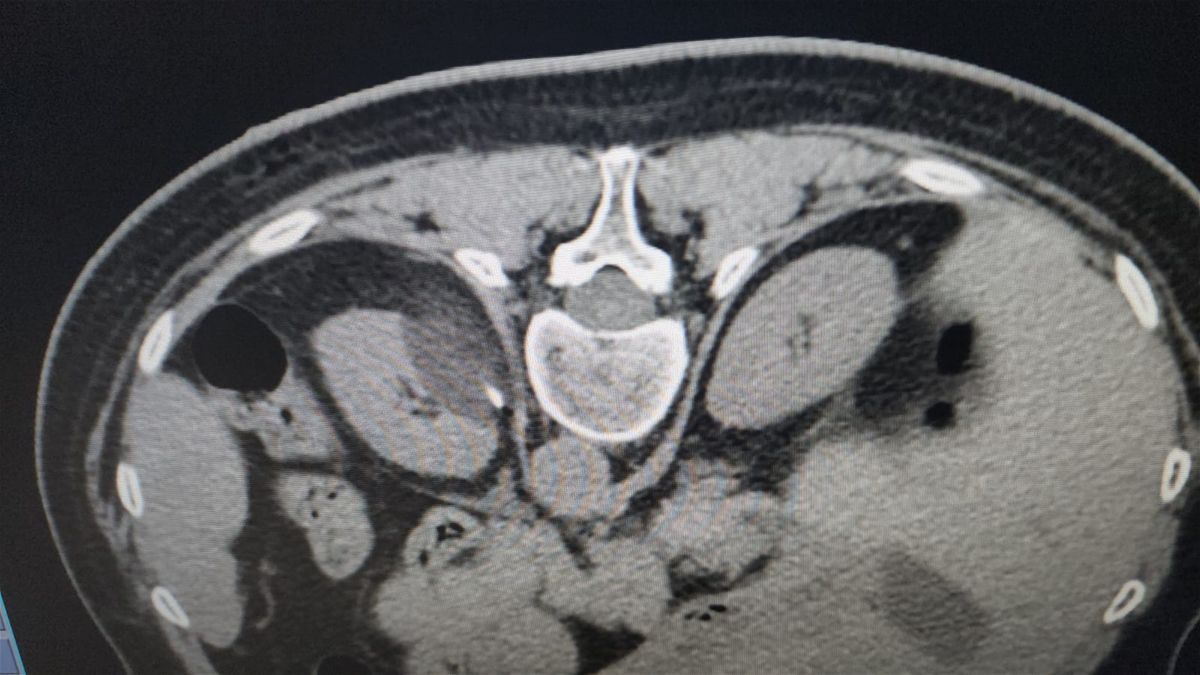

فكيف يتم التشخيص والتدخل الطبي؟ يقوم الأطباء بالتشخيص قبل العملية وبعدها بواسطة "الصورة النووية"، ثم تتم المقارنة بين كل المراحل من الناحية التقنية، للوصول الى مرحلة إدخال مسابير التبريد الى مكان الورم، وذلك من خلال ضخ غاز قوي جدا يُسمى غاز "الارغون" بضغط كبير وعبر أجهزة متطورة، وذلك تحت مراقبة مباشرة، ليتم تدمير الأورام عن طريق تجميد نسيج الورم، بدرجة حرارة منخفضة للغاية (تصل إلى 160 تحت الصفر)، باستخدام تقنية التصوير.

يتحدث مدلج عن العلاج مشيرا الى انّ الجراحة بالتبريد هي من أهم التقنيات المستخدمة اليوم في العالم لاستئصال الأورام الخبيثة والحميدة في الجسم. ويقول: "الأهم انّ العملية تتم من دون فتح جراحي، وانما عبر أجهزة متخصصة إضافة الى مسابير التبريد التي تدخل مباشرة الى المنطقة المصابة وتقوم بإنشاء كرة جليدية، هذه الكرة تتدنى فيها الحرارة بالناقص 40 درجة وكفيلة بكي كل الخلايا المتورمة التي يجب اصابتها".